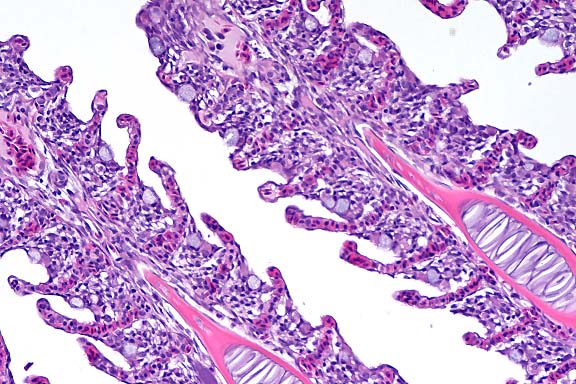

100x

obj

- Case 8-3. Kidney. One or more refractile protozoa

are found within many RBCs of congested interstitial capillaries.

There is fibrillar to amorphous proteinaceous material within

a collecting duct.

40x

- Case 8-3 . Kidney. The glomerulus contains increased

numbers of mesangial cells which compress glomerular capillaries.

Adjacent tubules are filled with eosinophilic material forming

hyaline casts.

Movat

Stain, 4x obj

- Case 8-3. Cardiac muscle. Myocardial muscle is partly

replaced by fibrous connective tissue (fibrosis).

4x

- Case 8-3. Colon. The lamina propria is markedly expanded

by diffuse hemorrhage which distorts and separates the mucosa

from the underlying tunica muscularis.